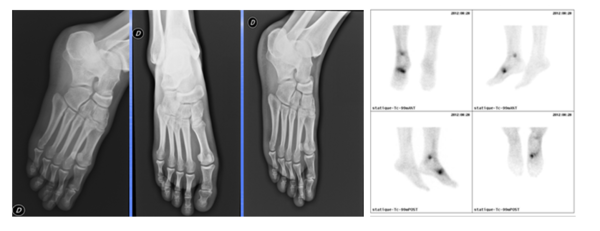

L’indication la plus probante du SPECT/CT en pathologie ostéo-articulaire bénigne est la douleur post-traumatique persistante malgré une radiographie standard négative(1). La technique permet en effet de dépister avec une très grande sensibilité, ou a contrario d’exclure formellement, une lésion osseuse fracturaire, avec ou sans déplacement. Les figures 3a à 3d illustrent parfaitement cette indication dans le cas d’un patient sportif s’étant présenté pour douleurs post-traumatiques et chez qui la radiographie standard se révélait normale, au contraire du SPECT-CT qui mettait en évidence deux fractures, tibiale distale et métatarsienne (fig. 3c et 3d).

Figure 3a à gauche - Radiographies normales suite à un trauma sportif

Figure 3b à droite - Scintigraphie planaire pathologique

Figure 3c -  SPECT/CT révélant une fracture rebord postérieur tibia

Figure 3d - SPECT/CT révélant une fracture base 1er MTT